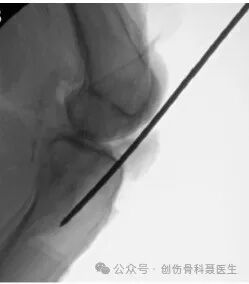

Incision & Entry Point: With the knee flexed to approximately 30°, the ideal entry point is located at the center of the intercondylar notch, approximately 1.2 cm anterior to the femoral attachment of the posterior cruciate ligament (consistent with the axis of the medullary canal).